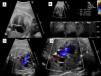

Se evidenció constricción precoz del ductus arterioso en un total de 7 gestantes, todas ellas se diagnosticaron en el tercer trimestre, con una edad gestacional media de 35,4 semanas. Las características de las gestantes se muestran en la tabla 1. Tras retirar el factor desencadenante (5/7) la evolución fue satisfactoria. Uno de los fetos presentaba restricción severa al flujo ductal grave con dilatación y disfunción de cavidades derechas e insuficiencia tricuspídea severa (fig. 1), que persistió en el periodo neonatal y que se normalizó en los controles posteriores en la consulta.

Constricción severa precoz del ductus arterioso. A) Plano de 4 cámaras donde se muestra dilatación de cavidades derechas con abombamiento de la membrana del foramen oval hacia la aurícula izquierda. B) Doppler a nivel del ductus arterioso donde se objetiva flujo continuo con aumento de velocidad en sístole y diástole. C) Insuficiencia tricuspídea severa. D) Plano de la V donde se objetiva disminución del diámetro ductal.